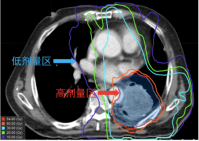

是一种新兴的精准放疗技术,通过三维网格化剂量分布,利用空间分割放疗技术,在肿瘤内部构建不均匀剂量分布。高剂量“晶格点”集中于肿瘤内部,形成“峰谷”结构,既能高效杀灭肿瘤细胞,又能通过低剂量区域保护正常组织。这种三维剂量分布突破了传统放疗的均匀照射模式,显著降低对周围器官的辐射损伤在肿瘤内部形成高剂量“晶格点”与低剂量区域交替的格局,实现对肿瘤细胞的精准杀伤,同时最大限度保护周围正常组织。

是一种先进的放射治疗技术,结合了适形放疗和调强放疗的优势,通过多叶光栅(MLC)等技术,使射线照射野的形状与肿瘤的三维形状精确匹配,确保射线仅覆盖肿瘤区域,减少对周围正常组织的照射;在适形的基础上,进一步调整射线束的强度分布。通过计算机算法优化,根据不同部位肿瘤的敏感性和周围正常组织的位置,精确控制射线剂量,使肿瘤内部剂量分布更均匀,同时降低对邻近重要器官(如脊髓、脑干、视神经等)的照射剂量。